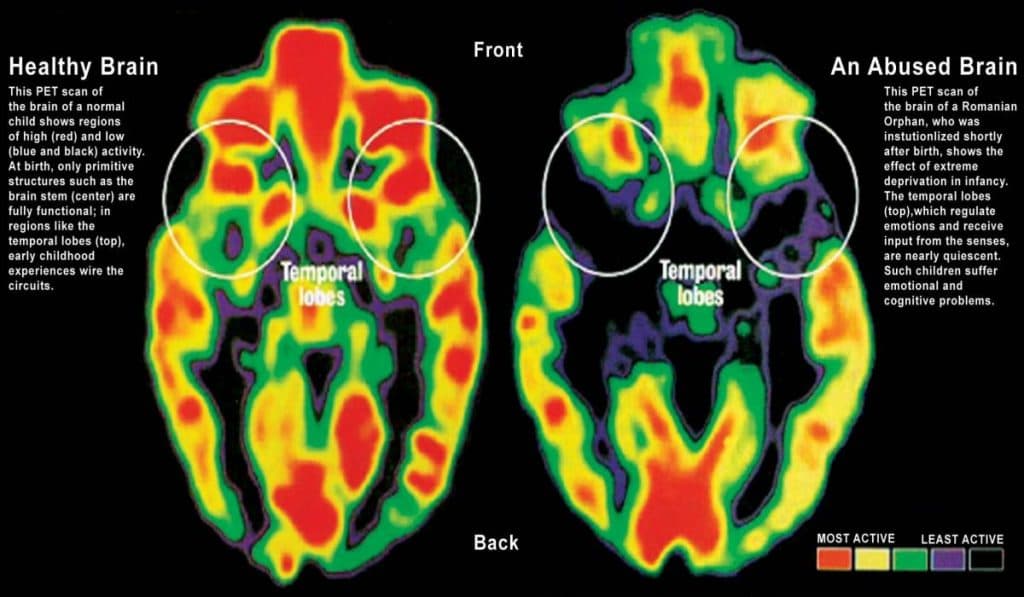

1. Early Attachment Shapes Brain Development

Attachment plays a major role in how children's brains develops.

- Secure attachment - helps the brain grow stronger in areas tied to emotion regulation and stress management.

- Insecure attachment - can shrink these areas by up to 30%.

Healthy caregiver bonds act as the foundation for emotional resilience, while insecure attachment can create lifelong difficulties in managing stress and emotions.

Source: Dr. H.T. Chugani. Newsweek, Spring Summer 1997

Source: Schore, A. N. (2001). Attachment and the regulation of the right brain.